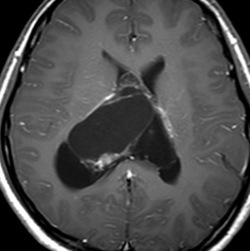

20代の男性の神経細胞腫です。側脳室の中のとても大きな腫瘍です。上段はガドリニウムという造影剤を入れた時のMRIです。下段の中央はCTですが,石灰化が見られます。脳外科の先生には,この脳室内腫瘍は一見transcallosal approach(経脳梁到達法)という手術で取れるように見えるかもしれませんが,そうではなくて,脳室の壁とくに上壁と側壁にくっついているのでなかなか取れません。この患者さんの場合は右の頭頂葉というところからtranscortical approach(経皮質到達法)で全摘出しました。後遺症もなく再発もなく術後10年が過ぎています。全部とれれば治ってしまう腫瘍です。